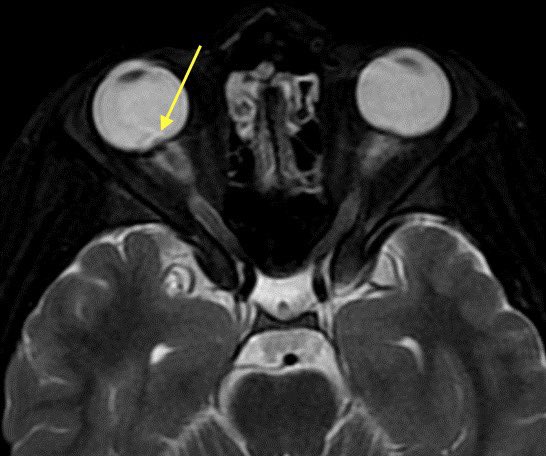

2️⃣Tortuous optic nerves and intraocular protrusion: again, increased pressure leads to protrusion, tortuous nerves, and prominent CSF surrounding the nerves within the sheath